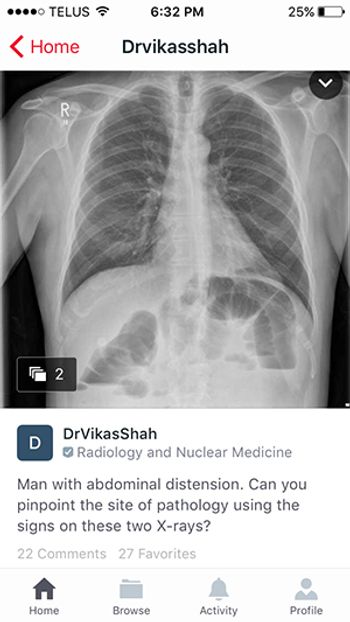

Image-based global networking tool connects physicians from all over the world.